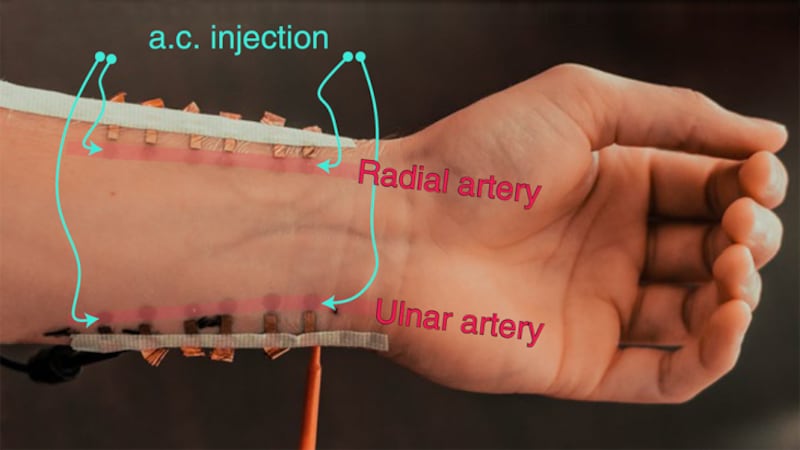

El tatuaje electrónico de los investigadores de la Universidad de Texas en Austin y la Universidad A&M de Texas puede llevarse cómodamente en la muñeca. Proporciona mediciones continuas de la presión arterial con un nivel de precisión que supera a casi todas las opciones disponibles en el mercado.

Según los científicos, el tatuaje electrónico es cómodo de llevar durante largos periodos de tiempo y no resbala.

“El sensor del tatuaje no pesa y es discreto. Lo colocas ahí. Ni siquiera lo ves, y no se mueve”, afirma Roozbeh Jafari, de la Universidad de Texas A&M.

-Se adhiere al cuerpo del paciente, muy cerca de la muñeca.